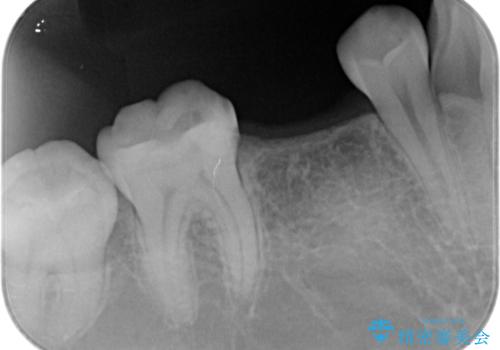

インプラント治療

- 過去に抜けてしまった歯のところにインプラントを入れたいとの事で来院。

CTで確認したところ骨の高さや厚みがインプラント埋入できる状態でしたのでインプラント治療を行いました。